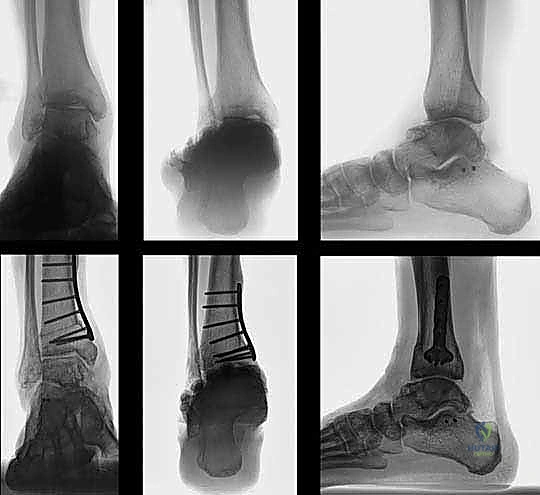

يُعد هذا من أكثر الأسباب شيوعاً في مجتمعاتنا. عندما يتعرض الشخص لكسر في عظم الظنبوب أو الشظية بالقرب من مفصل الكاحل، ولا يتم تجبيره أو تثبيته جراحياً بالزوايا التشريحية الصحيحة، يلتئم العظم في وضع معوج.

مثال سريري واقعي: مريض تعرض لكسر في الظنبوب والشظية قبل 26 عاماً، وتم علاجه بشكل تحفظي (بالجبس) دون تصحيح كامل للزاوية. بعد مرور ربع قرن، تطور لديه تشوه فحجي (تقوس للداخل) مع آلام شديدة نتيجة تآكل الغضروف الداخلي. في مثل هذه الحالات، قطع العظم هو الحل الجذري.

- الأشعة السينية أثناء الوقوف (Weight-Bearing X-rays): هذه هي الخطوة الأهم. لا يمكن تقييم تشوه الكاحل بدقة والمريض مستلقٍ. يجب أخذ صور أشعة طويلة للساقين بالكامل لتحديد "محور التحميل الميكانيكي" وقياس زوايا التشوه بدقة متناهية (مثل زاوية TAS وزاوية TLS).

- تصحيح المحور: يتم فتح أو إغلاق الشق العظمي للوصول إلى المحور الميكانيكي السليم للكاحل. يتم التحقق من ذلك داخل غرفة العمليات باستخدام جهاز الأشعة السينية الفلوروسكوبي (C-arm).

- التثبيت الداخلي (Internal Fixation): بمجرد الوصول للزاوية المثالية، يتم تثبيت العظم في وضعه الجديد بقوة باستخدام شرائح معدنية متطورة (Locking Plates) ومسامير من التيتانيوم. هذا التثبيت القوي يضمن عدم تحرك العظم أثناء فترة الالتئام.